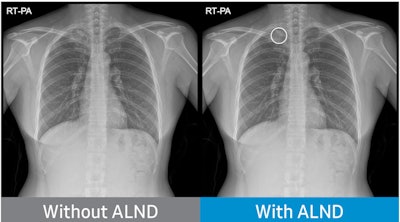

Samsung NeuroLogica has received U.S. Food and Drug Administration (FDA) 510(k) clearance for its Auto Lung Nodule Detection (ALND) tool, an artificial intelligence (AI)-assisted detection program for locating pulmonary nodules.

The tool is specifically designed to aid physicians in reviewing posteroanterior chest radiographs in adults for nodules 10 mm to 30 mm in size. The program is part of S-Station, the operating software installed on Samsung's digital x-ray imaging systems and includes an autorun option that automatically performs nodule detection after chest x-ray imaging.

In international clinical trials, ALND achieved a sensitivity of at least 80% identifying lung cancer in 600 chest x-rays, the company said.